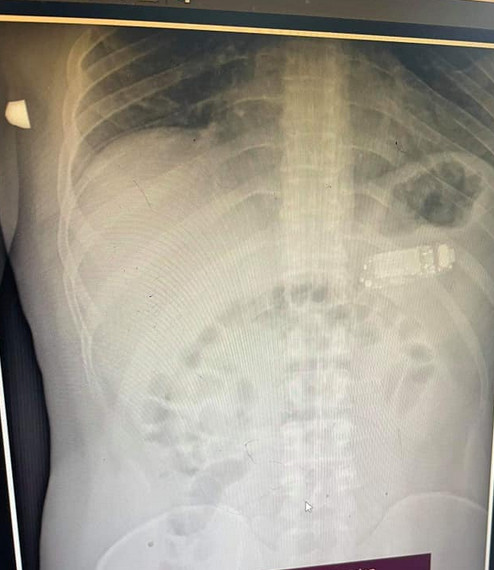

根據外媒《Metro》的報導,科索沃一名33歲男子因為肚子劇烈疼痛了4天,決定到普里什蒂納 (Pristina) 的醫院就診,醫生斯肯德 (Skender Teljaku) 替男子拍了腹部X光後,竟然看見一支手機完整的橫躺在男子的肚子裡,而這支手機竟然是人稱神機的「Nokia 3310」。

圖片來源 / Metro,下同

斯肯德醫生考量到手機真的大太了根本無法消化,還要擔心電池腐蝕性酸液隨時會流出,或是爆炸造成生命危險,因此和醫療團隊緊急用盡量不傷胃的內視鏡將手機取出。斯肯德先把手機用內視鏡分成三部份,再一一從嘴巴給拉出來,他坦言過程相當不容易,失敗的話只好用手術取出,但好在治療成功把手機順利夾了出來。

據了解,男子吞下的其實不是「Nokia 3310」,而是和它外型非常相似的仿冒品L8STAR BM90,比3310還要小一些,不過男子到底為何會吞下手機,至今都無法得到解答。醫生也公開了內視鏡取出手機的影片,讓網友們都嘖嘖稱奇。